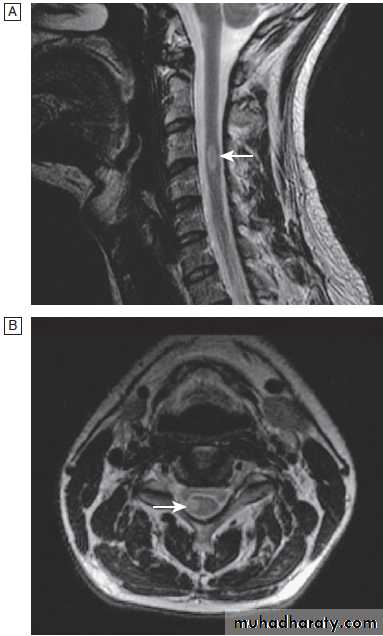

Cervical, thoracic and lumbar spine

Plain X-rays are useful in the investigation of trauma toVertebrae. MRI has transformed the investigation of these areas, since it can give information not only about the vertebrae and intervertebral discs, but also about their effects on the spinal cord and nerve roots.

Different techniques of imaging the cervical spine. A Lateral X-ray showing bilateral C6/7 facet dislocation. B Myelogram showing

widening of cervical cord due to astrocytoma (arrows). C MRI showing posterior epidural compression from adenocarcinomatous metastasis to the posterior arch of T1 (arrows).